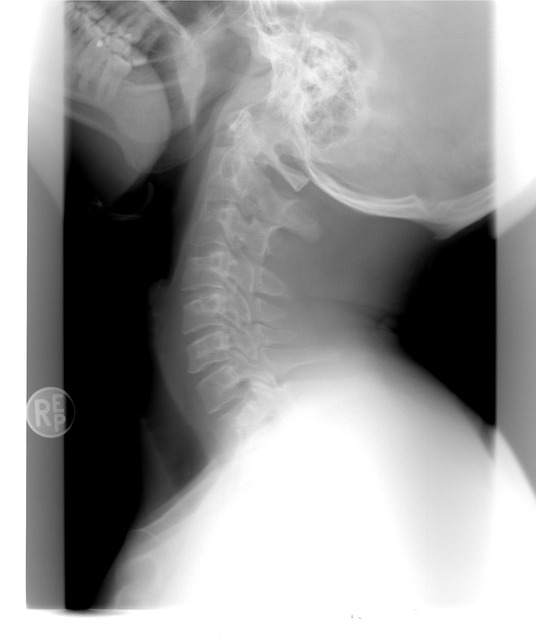

| 목 통증의 원인과 간단한 스트레칭 (0) | 2025.06.06 |